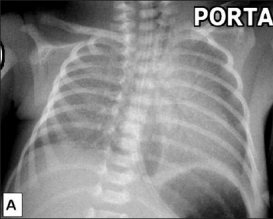

Which pediatric disorder will present with hyperinflation, patchy infiltrates and coarse streaking on chest x-ray? _____

Which pediatric disorder will present with overaeration, prominent pulmonary vascular markings and fluid in interlobar fissure on chest x-ray? _____